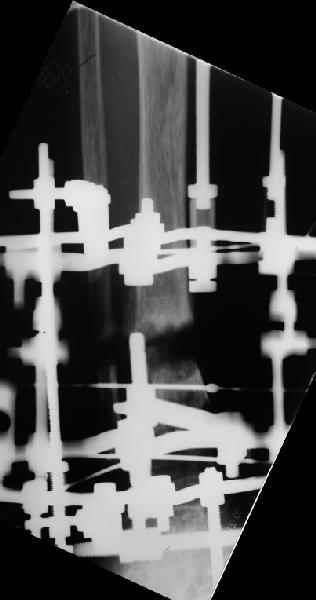

Аппарат - чтобы плавно исправить ось. В приложении - снимки на момент окончания коррекции в аппарате, фото с операции, и послеоперационная рентгенограмма.

Диаметр гвоздика 10,5 мм. Пришлось укорачивать до 23 см - уж очень миниатюрная дама, отверстия насверлил под 45 градусов, под 5 мм винты. По оси удалось сблизить до этого положения. Заперли гвоздь пока статически с планом через 2 месяца верхний винт убрать. Но это ей придется уже в Ташкенте сделать. Что скажете? Спасибо.

In attachment - x-rays at the end of alignment, the surgery, and result. The nail was cut to 23 cm. Four 45 degree holes were pre-drilled at the distal nail tip. The nail was locked statically

after some impaction. Dynamization is considered in 8 weeks. Any comments/critics?

NL> Amazing! How can you find the pathway of the nail through all those wires

NL> and the distal screws through so much hardware?

Some wires were intentionally inserted to leave needed space for the nail, some were removed at the moment of nail insertion. I inserted one distal screw and then removed the frame, then inserted rest ones.